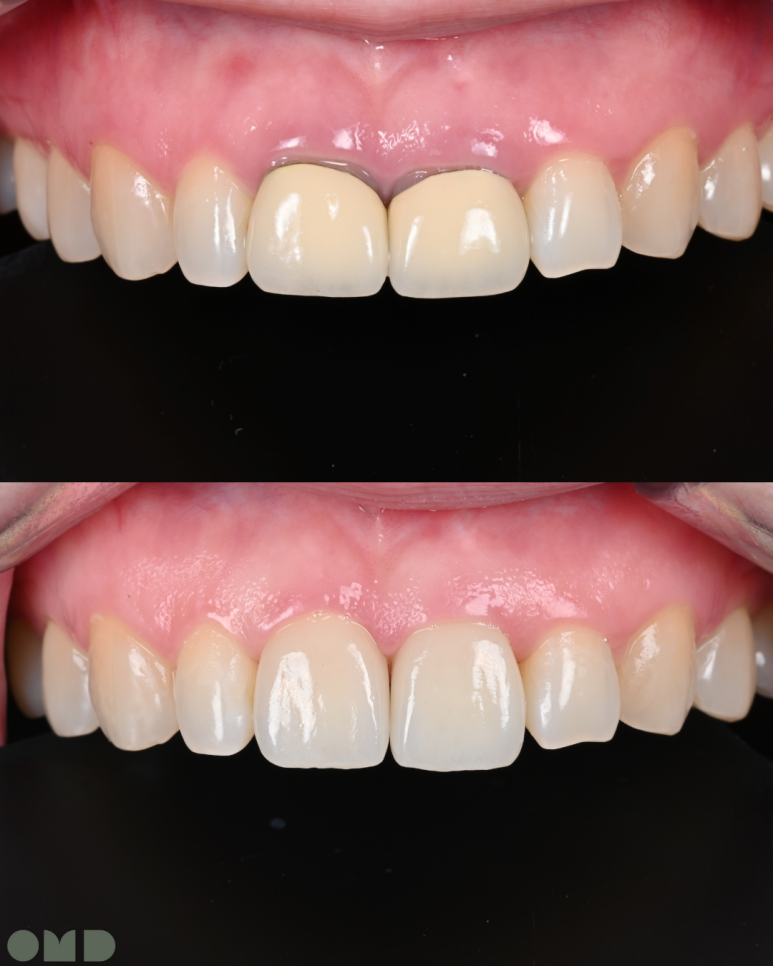

5. 최종 크라운 장착

새로 제작된 크라운을 장착합니다.

환자분께서 색상과 모양에 만족해하셔서 특별한 수정없이

치료를 마무리할 수 있었습니다.

25.09.11 치료 후

앞니 크라운은 심미적으로 가장 눈에 띄는 부위라

작은 차이에도 만족도가 크게 달라집니다.